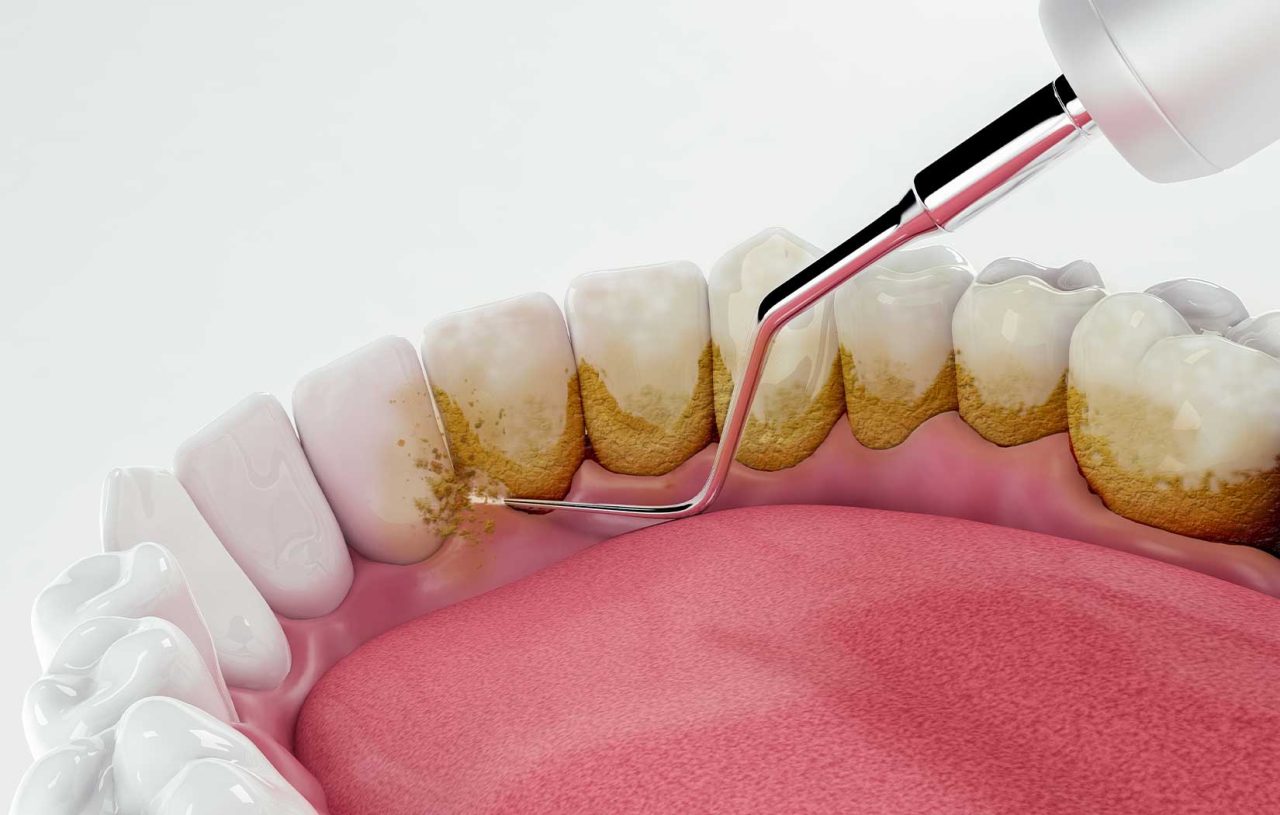

Entre os desafios que o cirurgião-dentista enfrenta na rotina clínica, algumas condições periodontais se destacam pela gravidade e pelo impacto imediato na qualidade de vida do